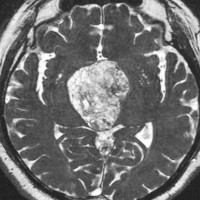

典型的なMRIの画像です

下垂体腺腫のMRIです。両側の視野障害(両耳側半盲)のために手術を受けた患者さんのものです。この腫瘍は非機能性腺腫といってホルモンを出さない腫瘍でした。少し大きめでしたが全部取れて視野の障害はよくなりました。

左の2枚はガドリニウム造影剤を使って写したもので腫瘍の形がよくわかります。右の1枚はT2強調画像と言います。MRIでは撮影の仕方によって見え方が違います。